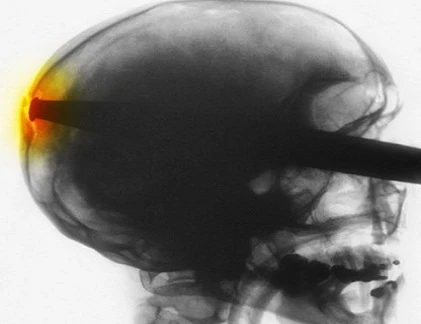

Một con dao cắm vào trong hộp sọ của một cậu bé 10 tuổi tại Camp Bastion ở tỉnh Helmand, Afghanistan trong bản chụp X-quang. Con dao sau đó đã được gỡ bỏ bằng cách phẫu thuật.